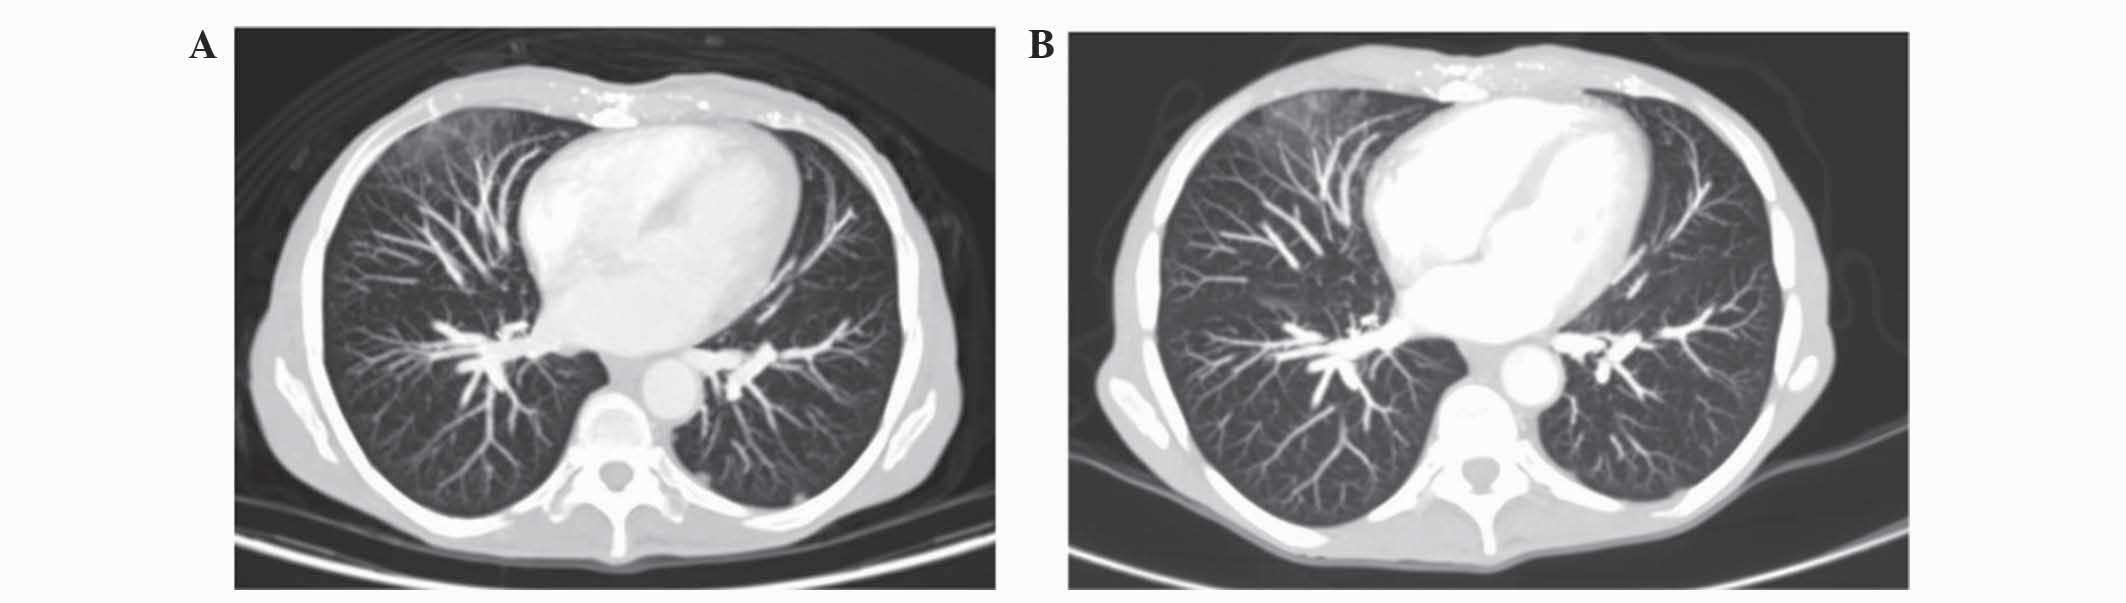

Nab‑paclitaxel plus gemcitabine as first‑line palliative chemotherapy in a patient with metastatic pancreatic cancer with Eastern Cooperative Oncology Group performance status of 2

Metastatic pancreatic cancer (PC) has been associated with a considerably poor prognosis. Due to its toxicity, first‑line combination chemotherapy is limited to patients with a good performance status (PS). Previously nab‑paclitaxel plus gemcitabine has been demonstrated to improve the overall survival rate in patients with advanced pancreatic cancer with a good PS. The present study reports a case of a patient with metastatic PC with a poor PS (Eastern Cooperative Oncology Group 2) and a complex set of comorbidities treated with nab‑paclitaxel plus gemcitabine as a first‑line palliative therapy. Adjusted doses of nab‑paclitaxel plus gemcitabine reached a favourable clinical, radiological and biochemical response in the present patient, which increased the quality of life for the patient. Eventually, the patient succumbed to acute cholangitis. Based on the results of the present study, nab‑paclitaxel plus gemcitabine appears to be a favourable treatment as first‑line palliative chemotherapy for patients with metastatic PC, comorbidities and poor PS.

Figure 1

Figure 2